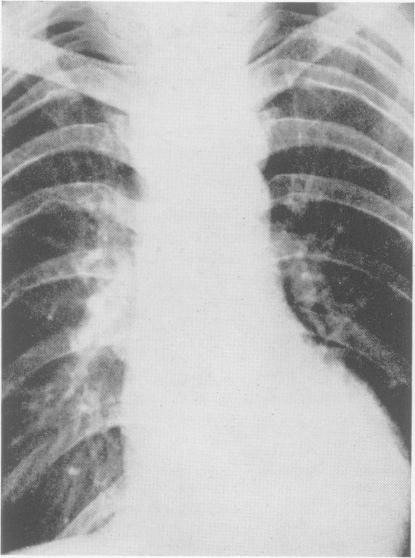

Radiology in the investigation and management of hypertension.

Postgrad Med J. 1958 Oct;34(396):514-23 passim. doi: 10.1136/pgmj.34.396.514.